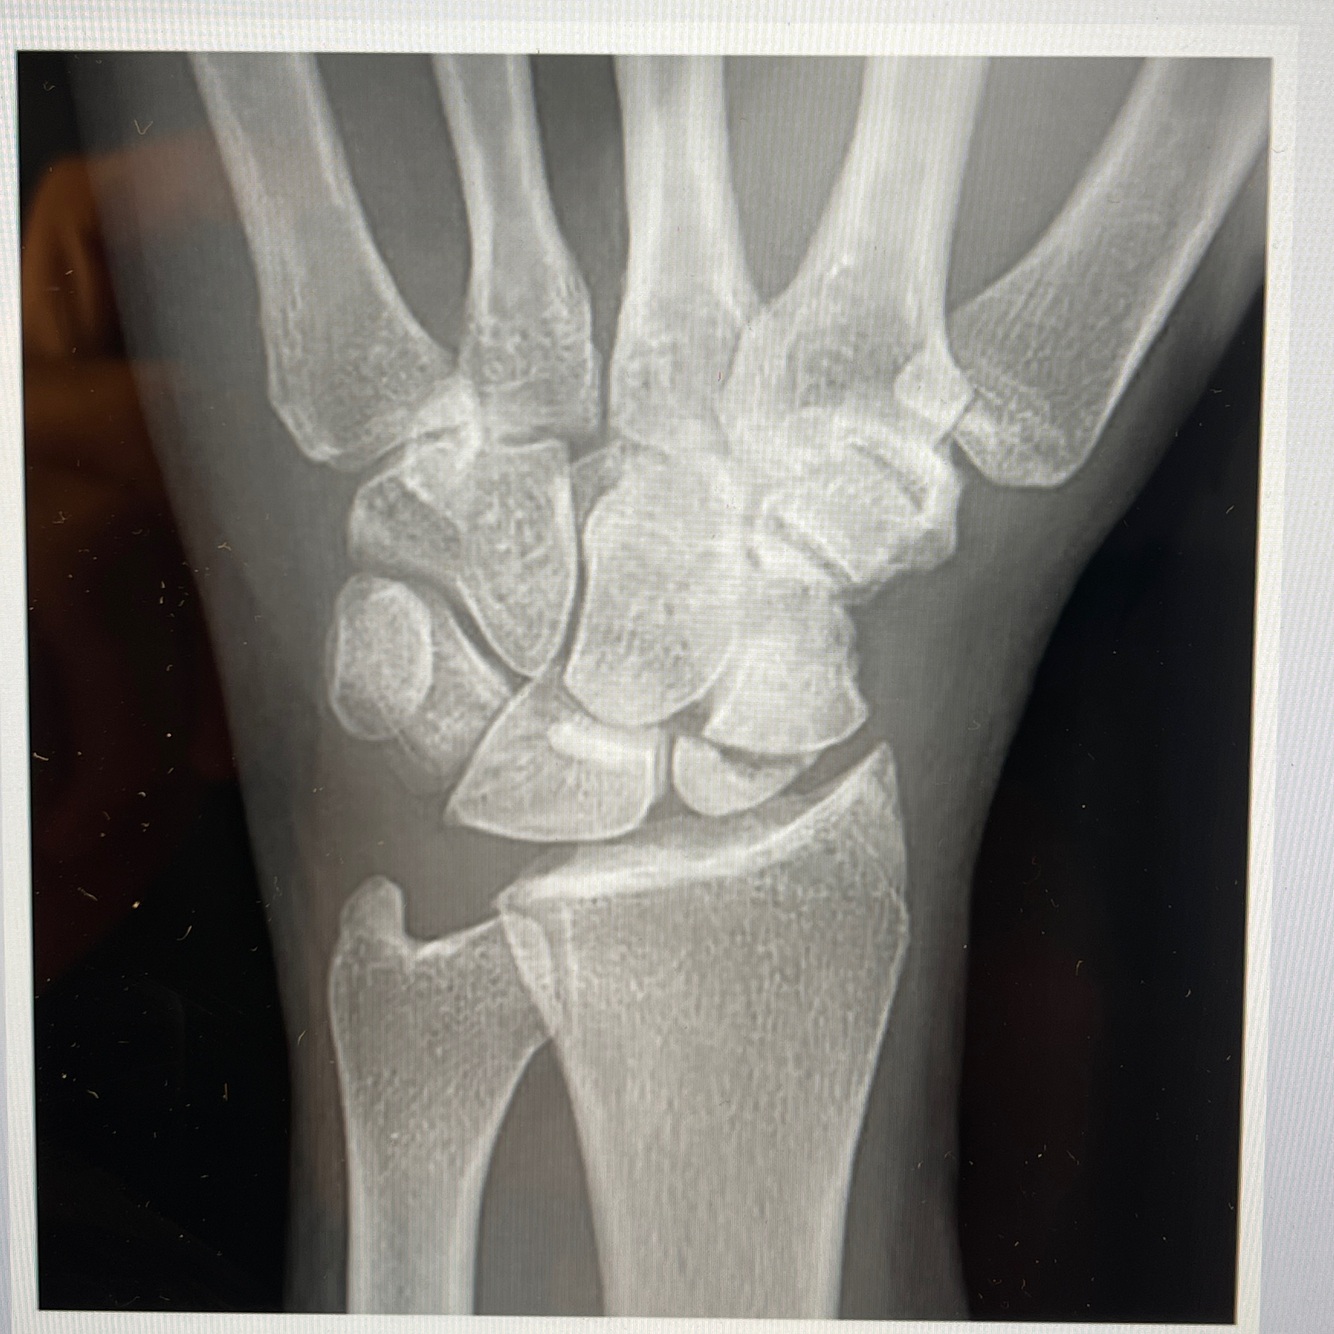

A